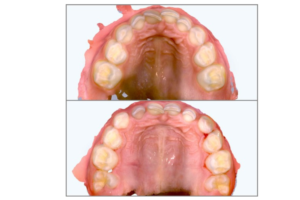

- Early orthodontic intervention is used only when indicated in patients who are screened, have a diagnosis of signs and symptoms of SDB and have been diagnosed with inadequate airway anatomy

- Early interventional orthodontics is used to better the anatomy only, this, in turn, will help the other treatments needed to better airway health

The use of Early Interventional Orthodontics in helping better the anatomy of the airway is an important part of airway health; it can be performed by trained dental professionals regardless of a board certification in orthodontics.